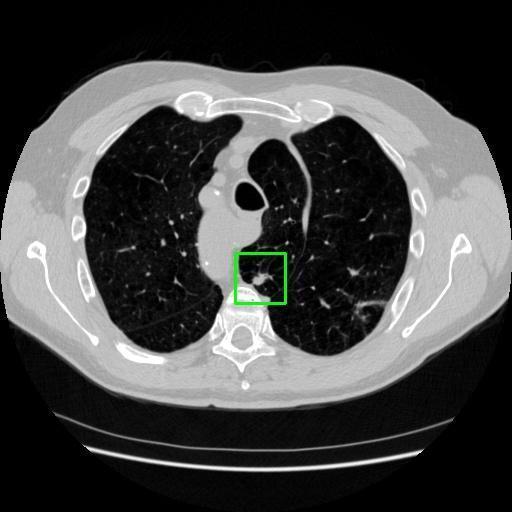

We developed an AI-based system using deep learning models for analyzing lung CT scans to detect and classify pulmonary nodules. We chose the YOLOv11 architecture for its enhanced object detection capability and adapted it specifically for medical imaging, incorporating pixel-level precision and severity classification.

Classification into three severity levels with colored bounding boxes.

Designed a severity classification system that categorizes nodules into null, moderate, and severe using colored bounding boxes, assisting in rapid clinical decision-making.